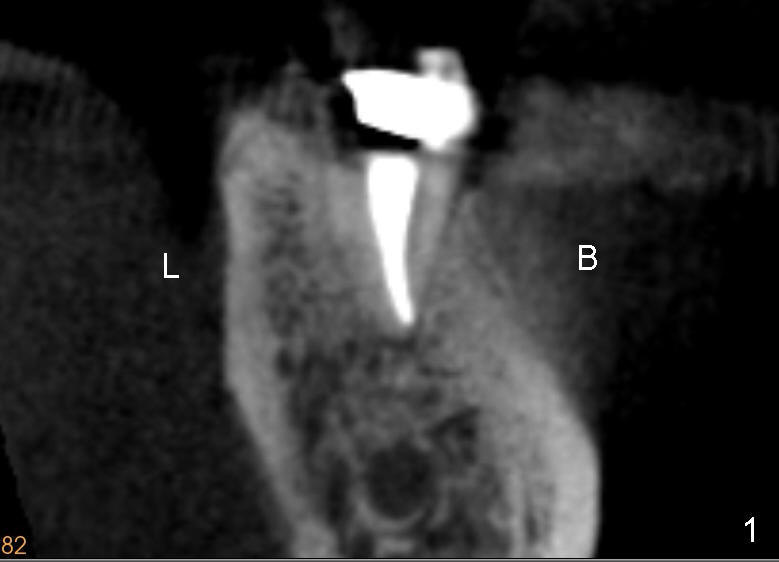

The root of the lower molar is more or less situated buccally, as shown in Fig.1 (coronal section of the distal root of a 2nd molar). If osteotomy follows the path of the original socket (black shadow in Fig.2 (Fig.1 after extraction)), the buccal plate (<) would be thin and low when an implant is placed.